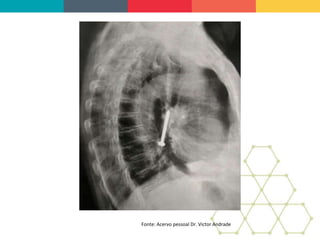

BACKGROUND: Bronchobiliary fistula

(BBF) is a rare condition in which there is

communication between the biliary

system and bronchial tree. The etiology

most commonly found is secondary to

liver or subphrenic abscesses, infected

by echinococcus or amoeba. Can occur

secondary to transdiaphragmatic

migration of the biliary stent, placed on

biliary tract for the treatment of

obstructive jaundice, and also to liver

mucormycosis. BBF was observed as

postoperative complications of liver

resection for cholangiocarcinoma. It has

also been described arising from hepatic

hydatid migration into the lung through

the diaphragm. The management of this

condition should be conducted by a

multidisciplinary team and involves less

invasive alternatives such as endoscopic

therapy and transparietohepatic

drainage.

Endoscopic treatment of bronchobiliary fistula after

liver metastasis resection: Case report

OBJECTIVE: This study aims to report a

case of a patient who developed a

bronchobiliary fistula after surgery for

liver metastasis resection of advanced

colon cancer.

CASE REPORT: Patient 53 year-old, female, diagnosed

with advanced sigmoid colon cancer with liver metastasis

and was submited a rectosigmoidectomy associated with

hepatic trisegmentectomy. In the immediate postoperative

period, the patient developed a high-output biliary fistula

associated with choleperitoneum and subsequent

formation of subphrenic abscess drained externally.

Referred to our service for performing endoscopic

retrograde cholangiopancreatography (ERCP) by default

of obstructive jaundice and bilioptysis in moderate

quantity. The diagnosis of BBF was showing the

cholangiography and then confirmed by computed

tomography of the chest and abdomen. The endoscopic

treatment consisted of drainage of the bile duct; the

decompression was realized through wide papillotomy and

passage of a plastic biliary stent.

CONCLUSION: ERCP is a minimally invasive procedure

and choice in the treatment of bronchobiliary fistula with a

success rate close to 60%. The literature demonstrates

resolution of the fistula, with conservative treatments,

around five weeks. The patient progressed satisfactorily

with bilioptysis resolution and decrease the bilious flow

through the external abdominal drainage. A bronchoscopy

was performed after 15 days and did not show the

presence of bile secretion in the bronchial tree. In the

follow up of outpatient, didn't occurs any sign of

recurrence of the bronchobiliary fistula.